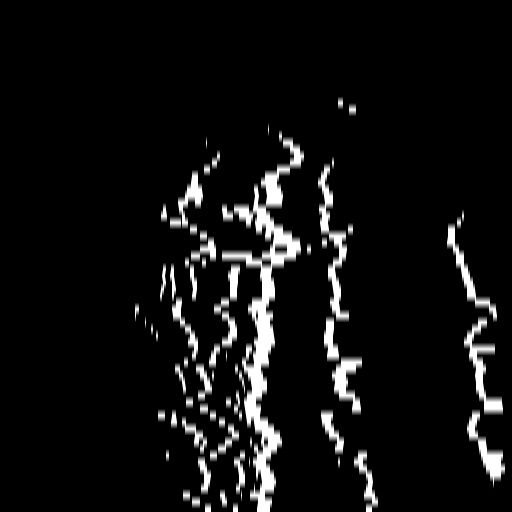

A.2 Temporal Coherency

Our method takes an entire X-ray video as input, thus producing segmentation results with better temporal coherency. Temporal coherency is essential for making medical diagnoses, especially when dealing with blood flow in vessels. Therefore, we conduct visual comparisons between our method and other compared methods by slicing horizontally or vertically and stacking the segmentation results. The results in Figure 11 show our method strikes a better balance between segmentation accuracy and temporal coherency. While other baseline methods either produce false segmentation results or do not maintain consistent prediction along the temporal dimension.